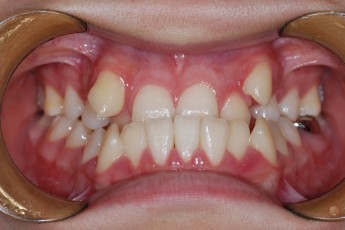

BEFORE & AFTER

- 덧니교정